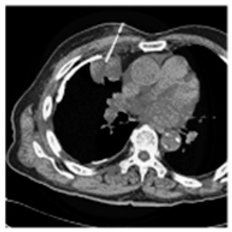

| Original Medical Images | |||||||

| Pair 1 | Pair 2 | Pair 3 | Pair 4 | ||||

![]() (1-9) PSNR = 44.14 | ![]() (1-10) PSNR = 41.90 | ![]() (1-11) PSNR = 40.09 | ![]() (1-12) PSNR = 41.41 | ![]() (1-13) PSNR = 42.24 | ![]() (1-14) PSNR = 40.35 | ![]() (1-15) PSNR = 40.79 | ![]() (1-16) PSNR = 40.84 |

| Shadow Images Produced by Using LSBs | |||||||

![]() (1-17) PSNR = 26.35 | ![]() (1-18) PSNR = 25.49 | ![]() (1-19) PSNR = 23.57 | ![]() (1-20) PSNR = 24.19 | ![]() (1-21) PSNR = 24.79 | ![]() (1-22) PSNR = 24.23 | ![]() (1-23) PSNR = 23.26 | ![]() (1-24) PSNR = 24.42 |

| Shadow Images Produced by Using Middle Bits | |||||||

![]() (1-25) PSNR = 18.97 | ![]() (1-26) PSNR = 19.95 | ![]() (1-27) PSNR = 14.10 | ![]() (1-28) PSNR = 13.84 | ![]() (1-29) PSNR = 16.66 | ![]() (1-30) PSNR = 13.23 | ![]() (1-31) PSNR = 13.38 | ![]() (1-32) PSNR = 14.75 |

| Shadow Images Produced by Using MSBs | |||||||